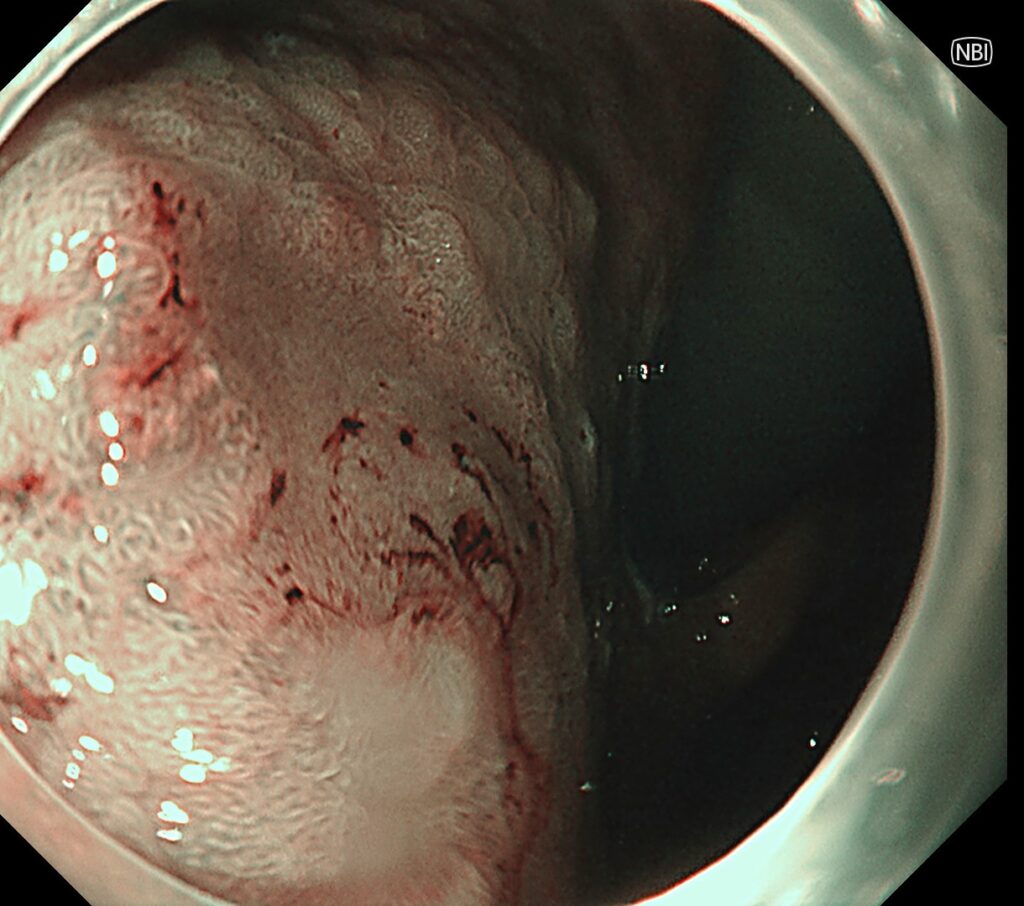

NBI観察では、高分化型腺癌(顔つきの良い癌)+中分化型腺癌(やや顔つきの悪い癌)の混在所見を認めます。